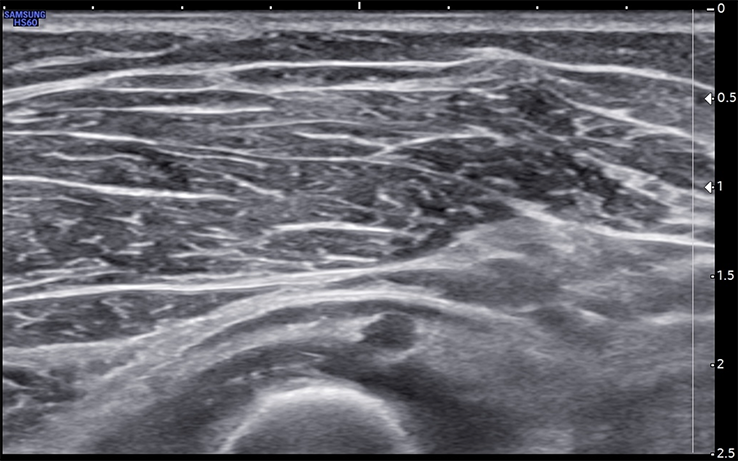

Unlabeled short-axis ultrasound image of the deep motor branch of the radial nerve a few millimeters distal to the arcade of Frohse.